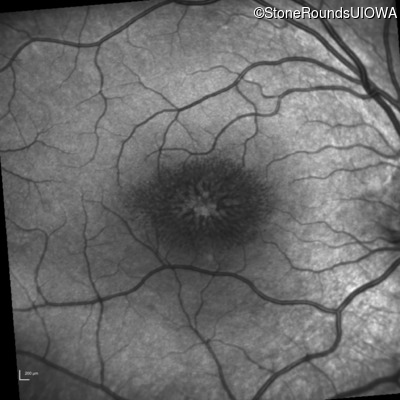

XL Retinoschisis (IIIB1)

XL Retinoschisis (IIIB1)

This 6 year old boy first experienced difficulty reading and seeing the blackboard at age 5.

| XL Retinoschisis | RS1 | Pro192His CCC>CAC | XL |